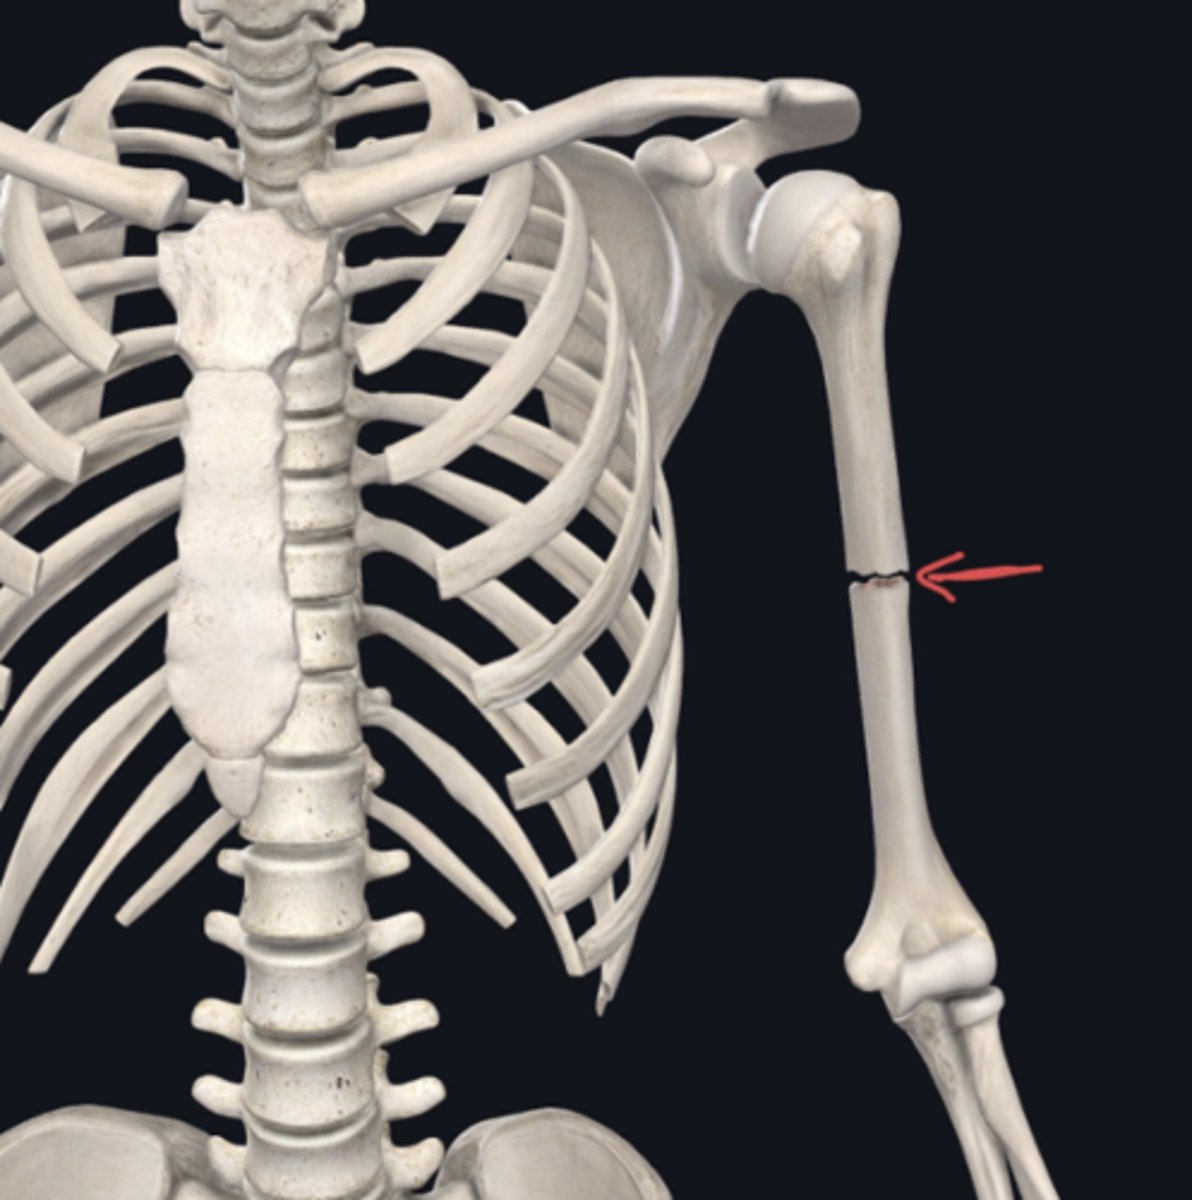

Identify the plane of section in which the indicated fracture has occurred. (Free response)

Sagittal (longitudinal also correct)